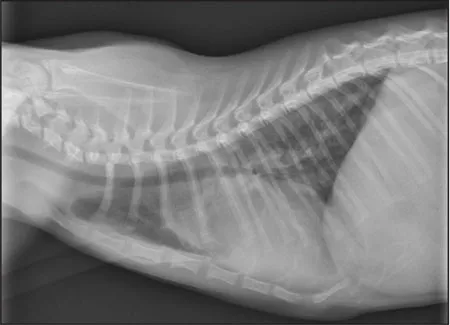

CASE 1.2 A 4-month-old female domestic shorthair cat with shallow breathing and a grade III/VI continuous murmur at the left cranial base. You obtain these thoracic radiographs: Fig. 1.2a, right lateral projection; Fig. 1.2b, dorsoventral projection.

1 What are your radiographic findings?

2 What is your radiographic diagnosis?

3 Is additional imaging needed?

1.2a

1.2b